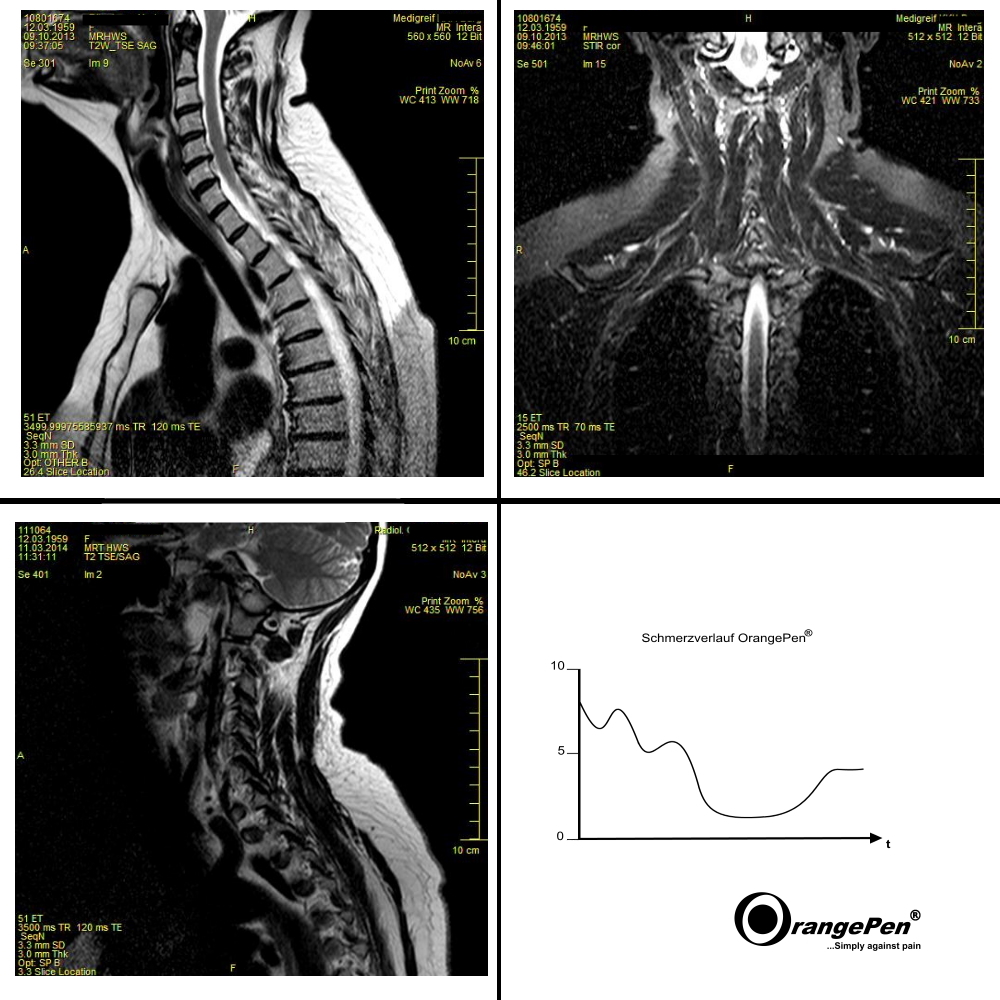

Years of neck pain

Years of neck pain treated with OrangePen®

Even with chronic diseases something can be moved. Integrate the OrangePen® into a multimodal pain therapy concept. The OrangePen® can be combined with all therapies. Only the use of the OrangePen® has brought the desired success here.